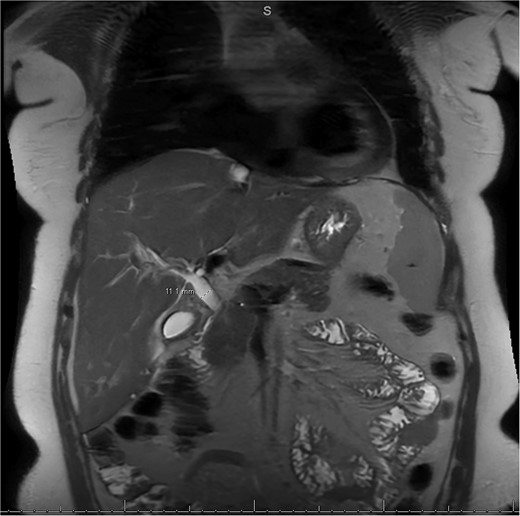

MRI/MRCP from second hospitalization demonstrating liver and kidney cysts.

A 49-year-old female with a history of ADPKD and multiple liver cysts, 13-months status post subtotal cholecystectomy, endoscopic retrograde cholangiopancreatography with biliary sphincterotomy and balloon stone extraction, presented to the emergency department with fever and a 4-day history of discomfort in the right upper quadrant. At the time of the initial cholecystectomy, total cholecystectomy could not be performed due to extensive adhesions, and subtotal cholecystectomy with complete evacuation of the stones was done instead. Magnetic resonance cholangiopancreatography (MRCP) done at that time showed a dilated common bile duct (CBD) to 1.5 cm, intra and extrahepatic biliary dilatation, multiple liver cysts measuring up to 2 cm, and multiple stones in the CBD, including at the level of the ampulla (Fig. 1). Computerized tomography scan at the time of the second admission showed acute cholecystitis and she had mildly elevated transaminases, but there was no evidence of cholestasis or pancreatitis. MRCP showed minor proximal intrahepatic biliary dilation and cholelithiasis but no duct calculi (Figs 2–4). A laparoscopic cholecystectomy was attempted with extensive adhesiolysis between the gallbladder and surrounding omentum and mesocolon, but the cystic duct could not be isolated, and ultimately the cased was converted to open. While removing the gallbladder in a top-down fashion, a small bile leak was identified right at the closed end of the gallbladder remnant, where the bile duct was adhered to the gallbladder wall. Intraoperative cholangiogram was obtained through a small perforation in a right posterior bile duct at the site of attachment, which showed right posterior, right anterior and left hepatic ducts of equal size converged at a trifurcation (Fig. 5). The duct was repaired over a T-tube and observed throughout the rest of the case and no bile leak was identified. The gallbladder was opened along its lateral edge, revealing a hugely dilated cystic duct with ~10 to 12 marble-sized stones packed within the gallbladder remnant and cystic duct down to the juncture with the common bile duct. All the stones were removed and the safe portion of the gallbladder remnant was resected leaving the side attached to the bile duct in situ due to the Mirizzi anatomical variant. The cystic duct was oversewn along with the remnant of the gallbladder wall. Pathology showed acute-on-chronic cholecystitis with cholelithiasis. Repeat MRCP showed no retained stones in the biliary tree. The recovery course was unremarkable.